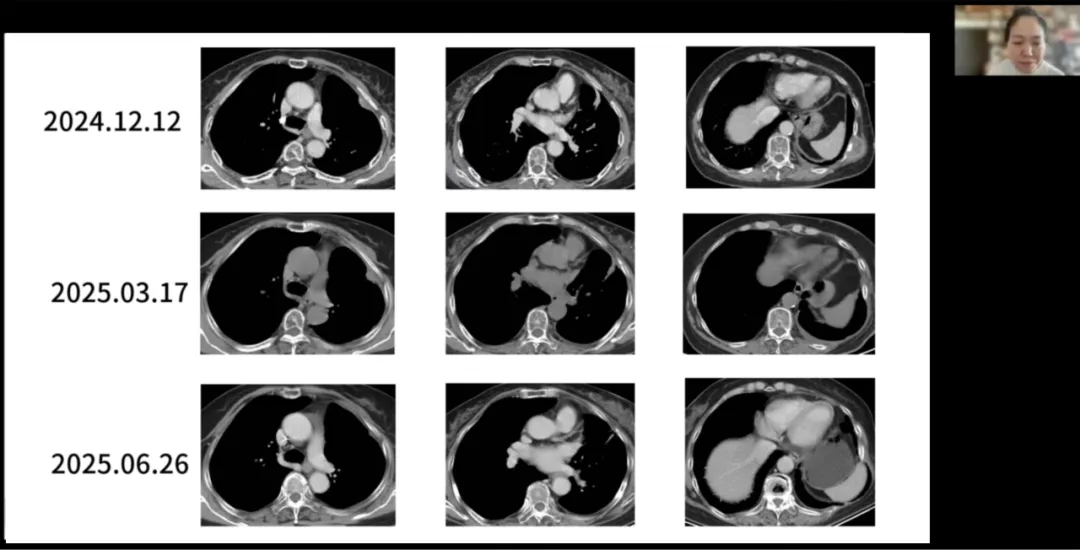

在王燕教授的主持下,宁夏医科大学总医院黄英教授汇报了一例EGFR突变晚期肺腺癌患者的全程管理过程。该例患者为51岁女性,2023年2月确诊为左肺低分化腺癌(cT2N3M1,IV期),伴有双肺及骨多发转移,基因检测显示携带EGFR 19外显子缺失突变。一线治疗采用第三代EGFR-TKI

在董玉梅教授的主持下,甘肃省肿瘤医院团队魏世鸿教授、白悦教授、王兴东教授、刘鹏教授和宋丽娟教授围绕该病例的治疗策略展开了深入的多学科讨论。专家们从影像学评估的规范性、病理学特征与组织学转化的可能性、晚期患者外科干预的有限角色,到放疗在EGFR阳性肺癌中的转化与姑息价值等多个维度,进行了系统而务实的交流,进一步丰富了该病例在精准诊疗与个体化决策中的临床启示。